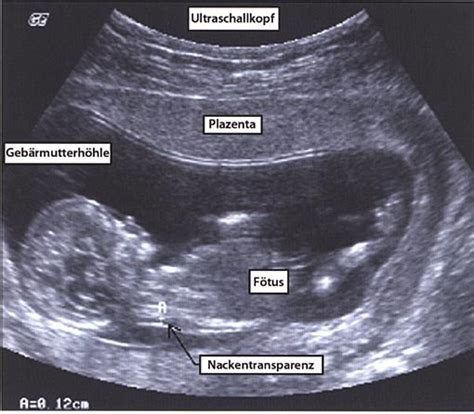

- Ultraschalluntersuchung: Feststellung, ob das Kind lebt und der Herzschlag sichtbar ist. Ab der 6. bis 7. Schwangerschaftswoche ist der Herzschlag meist erkennbar. Der Ultraschall kann auch Ursachen wie Blutergüsse hinter der Plazenta aufzeigen.